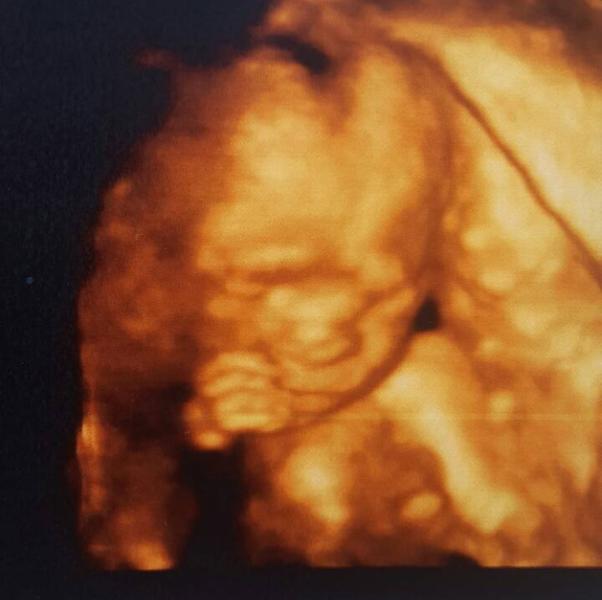

Ну что ж))) Была я сегодня на УЗИ у Справцевой😊 Всё супер👍 Все показатели в норме. Все органы на месте. Сидит моя принцесса👸 деловая у себя в домике и ей там очень даже уютно. Даже ноги "по деловому" сложила и руками их тянет к себе😄 Такая она сладкая, губки пухлые, носик пуговка😍 На папу похожа (это он сам так сказал) Вес 372 гр. Рост 21 см. Плацента поднялась. Шейка хорошая. Количество вод в норме. Короче тфу тфу тфу 😊 Теперь можно и мужа порадовать, заслужил за такое терпение😉